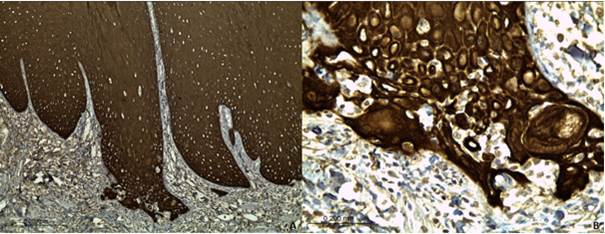

Immunohistochemical staining with pancytokeratin confirmed microinvasion; however, there was no evidence of infiltration into muscle tissue, blood vessels, or nerve tissue (Figure 3, A and B). The final diagnosis was microinvasive OSCC.

Figure 3. Immunohistochemical staining using AE1/AE3 antibody. A and B. Neoplastic epithelial cells superficially invading the lamina propria.

Histopathologically, microinvasive SCC is defined as being confined to the superficial stroma or lamina propria 26. In this case, basement membrane discontinuity was observed, along with the detachment of epithelial cells that remained superficial within the connective tissue. However, the presence of inflammatory infiltrate at the site can hinder visualization of the basement membrane’s integrity or obscure microinvasion, potentially leading to diagnostic uncertainty (27. In such scenarios, immunohistochemical staining with epithelial markers, such as pancytokeratin, can assist in detecting microinvasion, as demonstrated here.